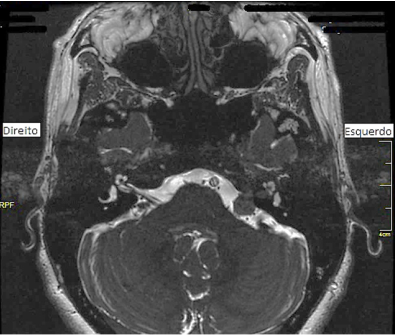

Observe a imagem a seguir e assinale a alternativa correta referente ao que ela evidencia.

enunciado 869679-1